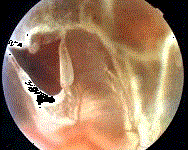

问题 患者,男性,45岁,双眼高度近视。左眼鼻下方飞蚊、闪光伴视野缺损1周就诊。检查发现左眼视网膜脱离。 (见图)如为孔源性视网膜脱离,则首先考虑裂孔位于 ( )

选项 A、鼻下方 B、黄斑部 C、颞下方 D、颞上方 E、鼻上方

答案 D